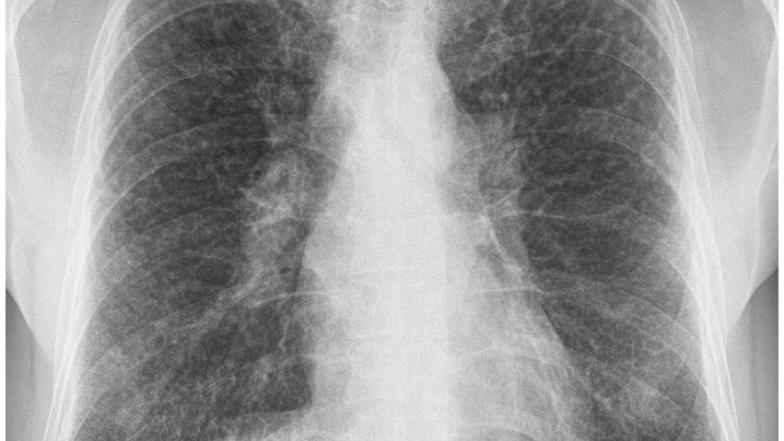

Sarcoidosis is a systemic inflammatory disease which is characterised by the formation of granulomas, clusters of immune cells, which most commonly affect the human lungs. Despite decades of research, there is still no single, definitive diagnostic test for Sarcoidosis. In practice doctors rely on the process of exclusion, first ruling out other conditions which have overlapping features, particularly TB, a widespread infectious disease caused by Mycobacterium tuberculosis (M.tb).